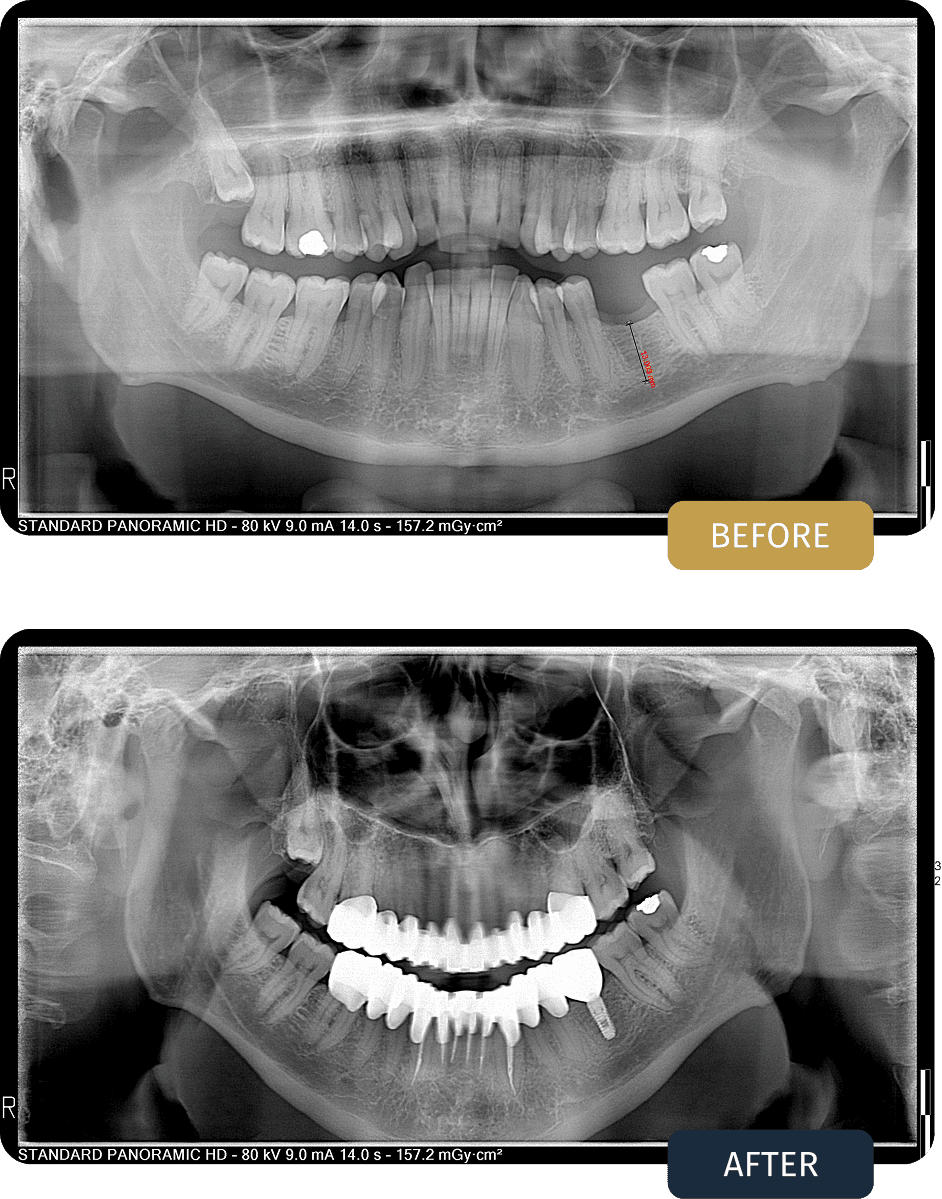

Clinical examination and panoramic imaging revealed that although significant restorative work was required, most natural teeth could be saved through a conservative approach combining root canal therapy, crowns, and fillings, with a single implant needed to replace one non salvageable tooth.

Post treatment panoramic imaging confirmed successful root canal treatments, stable implant placement, and well fitted crown restorations across both arches.

The restored bite showed improved balance, function, and long term structural support.